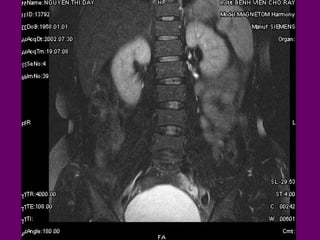

Di caên coät

soáng